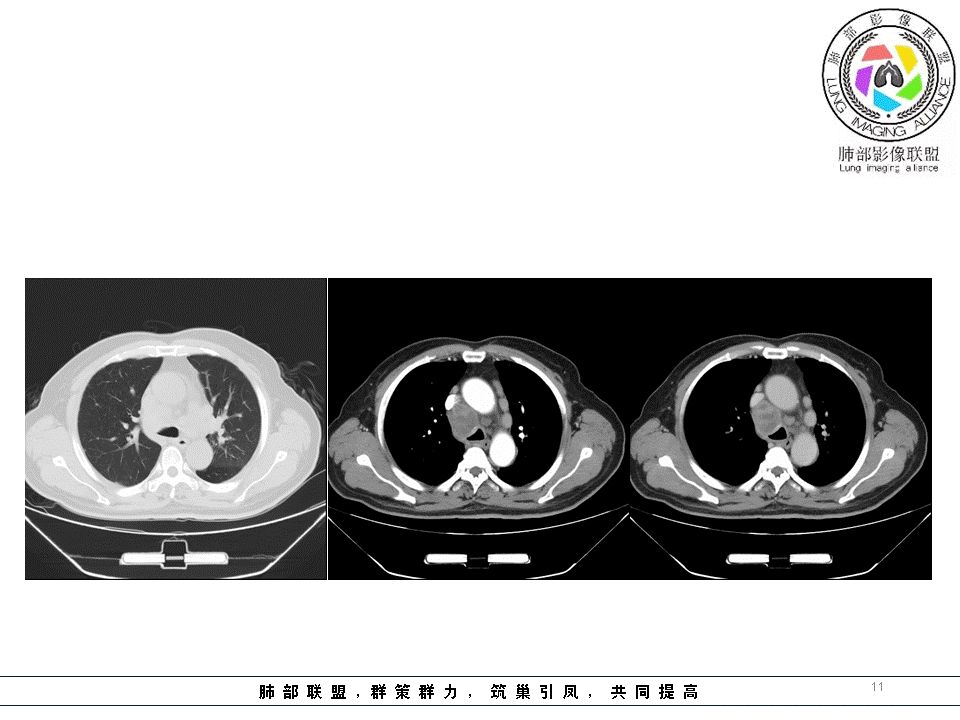

岁月:这个病例好,男性,62岁,症状2月,偶痰中带血。明显纵膈肿大淋巴结,超声颈部淋巴结,血流穿行。气管活检未见肿瘤细胞,炎性浸润为主。活检部位:左上叶、主气管粘膜。我们怎么考虑:1.小细胞肺癌,纵膈和左上肺病灶未提示,原因:原发病灶太小,没有活检到,小细胞按舟山理论首先不是支气管粘膜;不支持,坏死明显,尤其左肺门,转移常同侧,这例为颈部淋巴结都有。2.鳞癌,坏死符合,转移符合,分化符合,但活检不支持。3.淋巴瘤?4.结核?5.淋巴结增生症?

患者,男性,62岁,咳嗽咯痰2月余,半月前CT显示肺间质改变,CT肺窗左上肺斑片结节影,间质性改变,纵隔内多发肿大淋巴结,部分边界清晰,部分融合坏死,分析:1、病史较短,半个月,淋巴结融合坏死,结节病不首先考虑,2、没有冰冻纵隔,肿大淋巴结前纵膈不明显,淋巴瘤、小细胞肺癌转移不考虑,3、CD,一般肿大淋巴结,边界清晰,明显强化,一般无坏死,不考虑,结合临床,病史,纵隔多发淋巴结肿大,部分其内可见坏死低密度,左肺内病灶,气管镜,首先考虑淋巴结结核。

多发淋巴结肿大常规考虑5种病:结节病,淋巴结核,淋巴瘤,转移癌,LCD。CT:纵隔多发淋巴结肿大,轻强化,伴液化坏死,融合不明显,部分对称分布,脂肪间隙清楚,支气管镜下多发结节样隆起,伴粘膜水肿

诊断:首选结节病,

鉴别:第一鉴别淋巴结核,轻强化丶坏死,颈部肿大,但肺内无TB灶,常见年轻人发病

2:淋巴瘤:上纵隔多见,融合`包埋血管,不支持

3:转移癌:未见纵隔型肺癌的淋巴结肿大丶融合丶脂肪间隙消失,及小c冰冻肺门、纵隔,但气道有压迫性狭窄,彩超淋巴结门消失,不除外转移癌

4:LCD:浆细胞型,轻强化,坏死不明显,不支持。

患者老年男性,咳嗽、咳痰2月余,左肺门及纵隔肿块,主气道及左主支气管受压、受侵狭窄,病灶界清,有强化,有坏死,对血管破坏力不大,颈部及纵膈淋巴结多发肿大,综合考虑淋巴瘤(坏死不大支持)、小细胞癌、鳞癌(破坏力不大像),鉴别肺结核(临床症状和破坏力不大支持)、CD、结节病

中老年男性,纵隔及左肺门淋巴结肿大,部分可见坏死,结合颈部及锁骨上淋巴结肿大,1考虑恶性,转移瘤可能大,(坏死及年龄不支持淋巴瘤,2考虑结节病,会累及全身淋巴结

老年人,纵隔及两肺门区(左肺门为主)多发肿大淋巴结,仅腔静脉后淋巴结融合,内可见坏死,环形强化,并压迫气管轻度塌陷(说明较硬),其他淋巴结增大,但无明显融合。矽肺首先排除,年龄较大,淋巴结无钙化,肺内无任何病灶,结核也不是。淋巴瘤一般融合明显,不治疗坏死少见。CD强化明显,坏死也少见,综合考虑只有转移了,原发灶需继续寻找。也可能二元论,坏死淋巴结为结核,其他淋巴结为不典型的结节病。